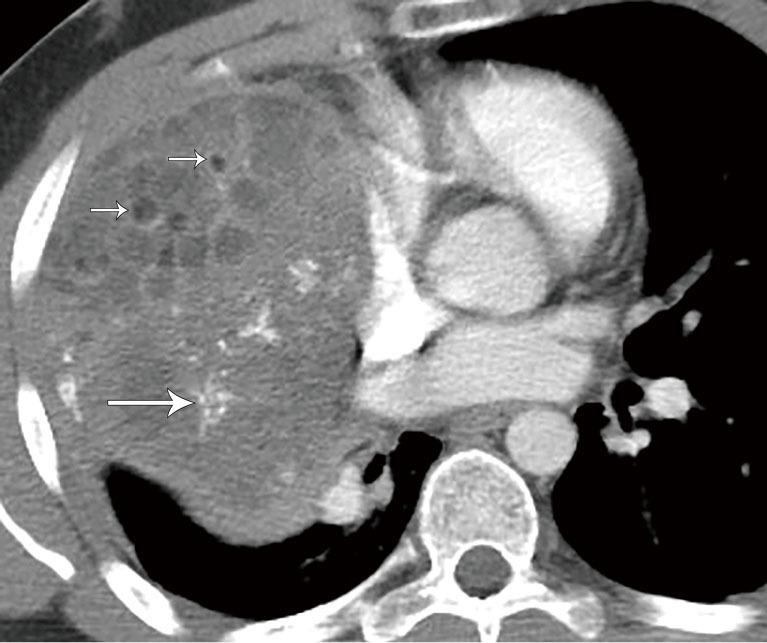

纵隔肿块及类似病变的多模态成像

Multimodality imaging of mediastinal masses and mimics.

A wide variety of neoplastic and nonneoplastic conditions occur in the mediastinum. Imaging plays a central role in the evaluation of mediastinal pathologies and their mimics. Localization of a mediastinal lesion to a compartment and characterization of morphology, density/signal intensity, enhancement, and mass effect on neighboring structures can help narrow the differentials. The International Thymic Malignancy Interest Group (ITMIG) established a cross-sectional imaging-derived and anatomy-based classification system for mediastinal compartments, comprising the prevascular (anterior), visceral (middle), and paravertebral (posterior) compartments. Cross-sectional imaging is integral in the evaluation of mediastinal lesions. Computed tomography (CT) and magnetic resonance imaging (MRI) are useful to characterize mediastinal lesions detected on radiography. Advantages of CT include its widespread availability, fast acquisition time, relatively low cost, and ability to detect calcium. Advantages of MRI include the lack of radiation exposure, superior soft tissue contrast resolution to detect invasion of the mass across tissue planes, including the chest wall and diaphragm, involvement of neurovascular structures, and the potential for dynamic sequences during free-breathing or cinematic cardiac gating to assess motion of the mass relative to adjacent structures. MRI is superior to CT in the differentiation of cystic from solid lesions and in the detection of fat to differentiate thymic hyperplasia from thymic malignancy.

纵隔可发生各种各样的肿瘤性和非肿瘤性疾病。影像学在纵隔病变及其类似病变的评估中起着核心作用。将纵隔病变定位到某个分区,并对其形态、密度/信号强度、强化情况以及对邻近结构的占位效应进行特征描述,有助于缩小鉴别诊断范围。国际胸腺恶性肿瘤研究小组(ITMIG)建立了一种基于横断面成像和解剖学的纵隔分区分类系统,包括血管前(前)、内脏(中)和椎旁(后)分区。横断面成像在纵隔病变评估中不可或缺。计算机断层扫描(CT)和磁共振成像(MRI)有助于对X线检查发现的纵隔病变进行特征描述。CT的优点包括广泛可用、采集时间短、成本相对较低以及能够检测钙化。MRI的优点包括无辐射暴露、软组织对比分辨率高,能够检测肿块跨越组织层面的侵犯情况,包括胸壁和膈肌、神经血管结构受累情况,以及在自由呼吸或电影式心脏门控期间进行动态序列成像以评估肿块相对于相邻结构的运动情况。在区分囊性病变与实性病变以及检测脂肪以鉴别胸腺增生与胸腺恶性肿瘤方面,MRI优于CT。